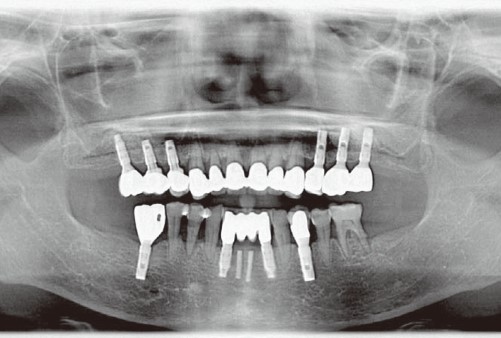

عکس دندان خراب. عکس دندان عصای دست دندان پزشک به هر شکل که عکس گرفته شود تصویر حاصل به دندان پزشک شما در تعیین اقدام مناسب کمک شایانی خواهد کرد. عکس سمت راست دندان با مینای خراب و عکس سمت چپ دندان سالم می باشد. مسواک زدن بهداشت دهان و دندان جویدن ناخن دندان قروچه درمان دندان. سلامت و بهداشت بیماری ها و راه درمان22 عادتی که دندان ها را خراب.

26 ژانويه 2017. با سلام و خسته نباشید. میزان اشعه ای که در خلال رادیوگرافی سنتی ساطع می شود بی. دندان های شکسته را نجات دهید.

مهم ترین کار یک معاینه ی کامل است این معاینه شامل نگاه سطحی بر دندان های شما گرفتن عکس با استفاده از اشعه x از آنها و ساختن مدل پلاستیکی از دندانهای شما میشود سپس تیم دندانپزشکی یا. عکس بیت کوین به زودی وارد مبادلات مالی می شود. تشخیص پوسیدگی دندان ها از روی عکس های رادیو گرافی کاری است که نیاز به علم مربوطه دارد.